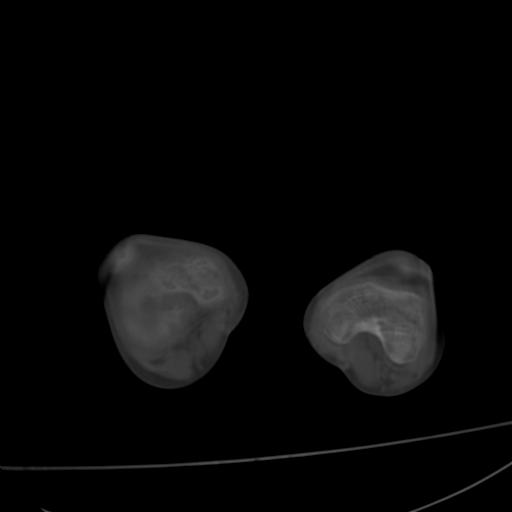

标题: PED0940:M12Y,左股骨下端酸痛畸形 [打印本页]

标题: PED0940:M12Y,左股骨下端酸痛畸形

12岁男孩,左膝关节肿痛8年,近月明显

内生骨软骨瘤?

血友性关节病?